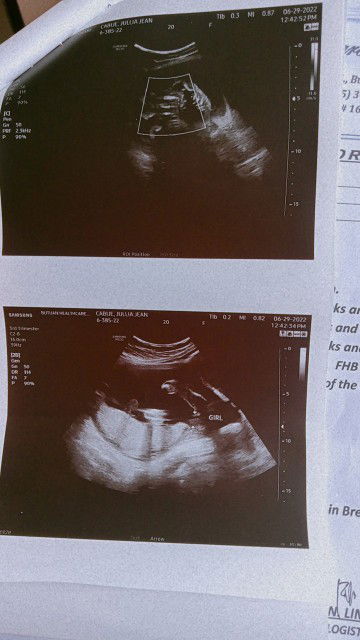

Woah! Finally I have a guts to share this here 🥰 Thankyou so much Lord God, For giving me this opportunity to become a Momma 😇❤️ It's a Girlll!!! 💞😍 See you soonest mylove Calia, Dada and I can't wait to see you 🥺 Be well in mami's tomb anak ko, Iloveyou so much! 💓 #ITSAGIRLLLLL #NovemberMommy #23weeks